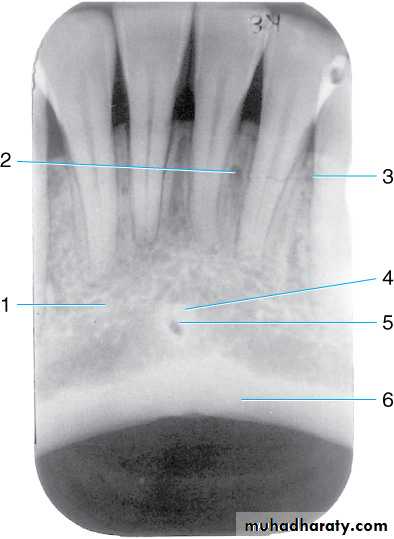

Radiograph of the mandibular midline area. This radiograph shows the (1) mental ridge, (2) nutrient canal, (3) nutrient foramen, (4) genial tubercles surrounding the (5) lingual foramen, and (6) inferior (lower) border of the mandible (radiopaque band of dense cortical bone).

*Often times when the vertical angulation is too excessive- you see the cortical bone